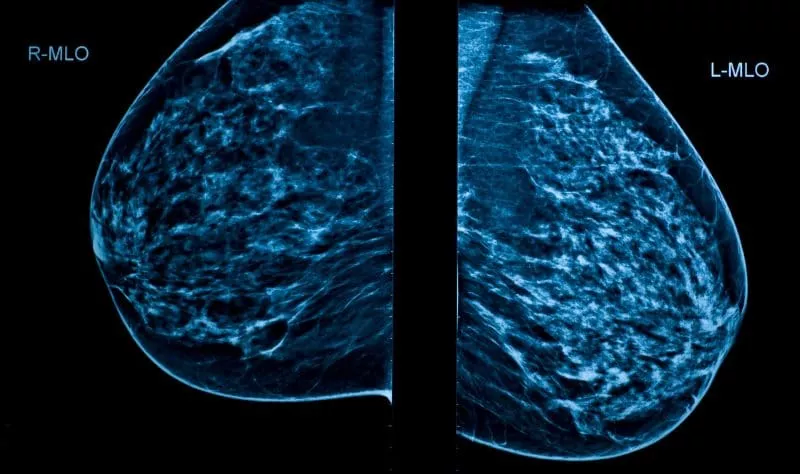

A 3D mammogram is an advanced imaging technique that takes 400 low-dose X-ray images from different angles to create a detailed, three-dimensional view of the breast. This approach provides a more comprehensive picture than traditional 2D mammography, helping radiologists to:

A 3D Mammogram takes up to 400 images of your breast (compared to 4 images in a 2D Mammogram) from different angles to create a detailed, three-dimensional view.